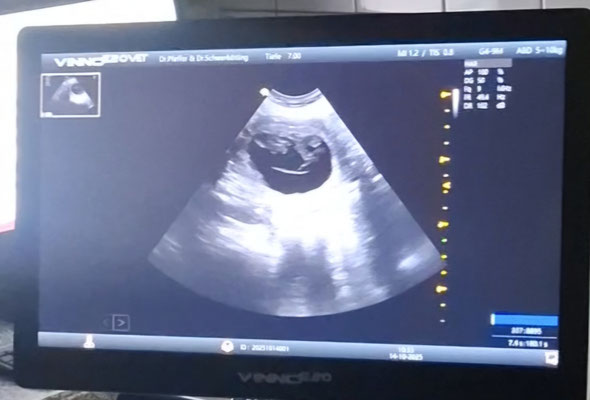

14.10.2025 Ultraschall Untersuchung.

Schon nach einem kurzen Blick in Ruby's Bauch war klar.

Sie ist tragend!

Doch wie viele es werden bleibt bis zuletzt spannend.

Hier müssen wir uns absolut keine Sorgen machen. Ruby scheint einen normalen Wurf zu erwarten, so auch die Aussage unserer Tierärztin.